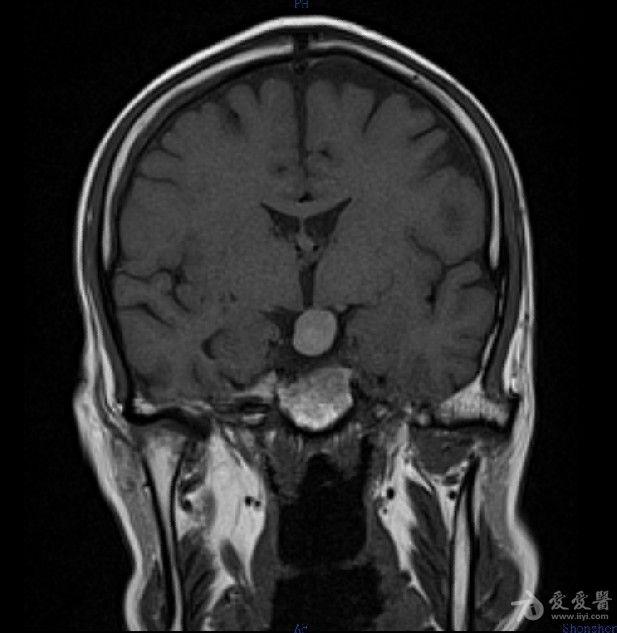

病例30:rathke囊肿